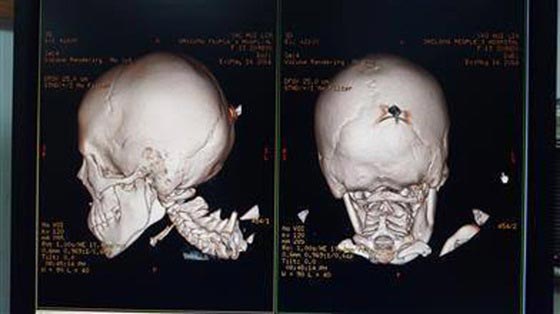

تعرضت فتاة تبلغ من العمر 12 عاما لحادث مروع كاد أن ينهي حياتها عندما ضربها زميل لها بسكين في الجزء الخلفي من رأسها. وفقا لموقع شنجهايست، دخلت الفتاة في شجار مع صبي في متنزه محلي بمدينة دونجقوان الصينية، ونجح الصبي بإنهاء الشجار بضربها بسكين طوله 15 سنتيمترا في الجزء الخلفي من رأسها، حيث بقي السكين ثابتا في رأسها دون أن يتسبب في قتلها.

تم نقل الفتاة إلى المستشفى ونجح الأطباء في إزالته بسحبه بعناية، وأكدوا في وقت لاحق أن حالتها مستقرة. في الوقت نفسه، قامت الشرطة باعتقال الجاني البالغ من العمر 13 عاما لكن لم يتم تجريمه بسبب صغر سنه، وقررت العائلتين تسوية المسألة خارج المحكمة، ومن المتوقع أن تدفع أسرة الصبي فواتير المستشفى.